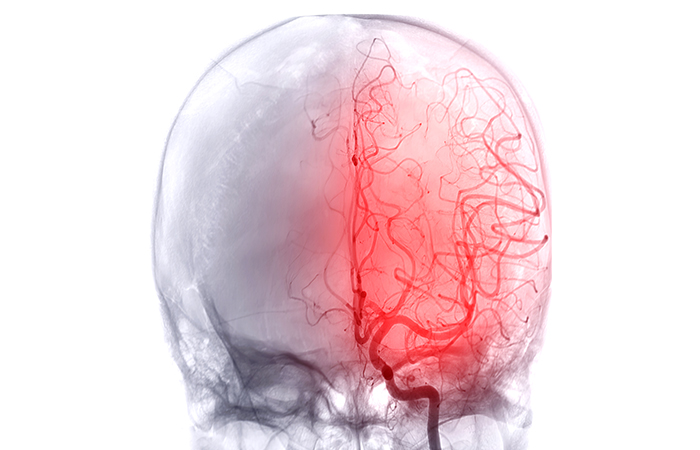

³úÇ÷°ü ÀÌ»óÀ¸·Î °©Àڱ⠹߻ýÇϸç,

¼Õ¹ßÀÇ ¸¶ºñ Áõ»ó ¹× È£Èí °ï¶õ µîÀÇ Áõ»óÀÌ

³ªÅ¸³ª´Â ÁúȯÀÔ´Ï´Ù.

ÈçÈ÷ ³úÁ¹ÁõÀ̶ó°í À߸ø ¾Ë°í ÀÖ´Â ³úÁ¹ÁßÀº ³úÀÇ °©ÀÛ½º·¯¿î Ç÷¾× ¼øÈ¯ Àå¾Ö·Î ³ªÅ¸³ª¸ç, °©ÀÚ±â ÀǽÄÀ» ÀÒ°í ¾²·¯Áö°Å³ª ¼Õ¹ßÀÇ ¸¶ºñ, Àú¸², ±¸À½(¹ßÀ½)Àå¾Ö µîÀÇ Áõ»óÀÌ ³ªÅ¸³ª´Â ÁúȯÀÔ´Ï´Ù. ³úÁ¹ÁßÀÇ ÀüÁ¶ Áõ»óÀ¸·Î ³ªÅ¸³ª´Â µÎÅëÀÇ °æ¿ì Æò¼Ò ¹ß»ýÇÏ´Â µÎÅë°ú´Â ´Ù¸¥ ¾ç»óÀ» º¸À̱⠶§¹®¿¡ °ü·Ã Áõ»ó¿¡ ´ëÇØ Á¤È®ÇÑ ÆÇ´ÜÀ» ³»¸®´Â °ÍÀÌ Áß¿äÇÕ´Ï´Ù. ³úÁ¹Áß Áõ»óÀÌ ³ªÅ¸³µÀ» ¶§ ÀûÀýÇÑ Ä¡·á°¡ ÀÌ·ç¾îÁöÁö ¾ÊÀ¸¸é ½ÉÇÑ °æ¿ì »ç¸Á¿¡±îÁö À̸¦ ¼ö ÀÖÀ¸¹Ç·Î ÀüÁ¶ Áõ»óÀ» Àß ÆÄ¾ÇÇØ Á¶±â¿¡ Ä¡·áÇÏ´Â °ÍÀÌ ¹«¾ùº¸´Ù Áß¿äÇÕ´Ï´Ù.